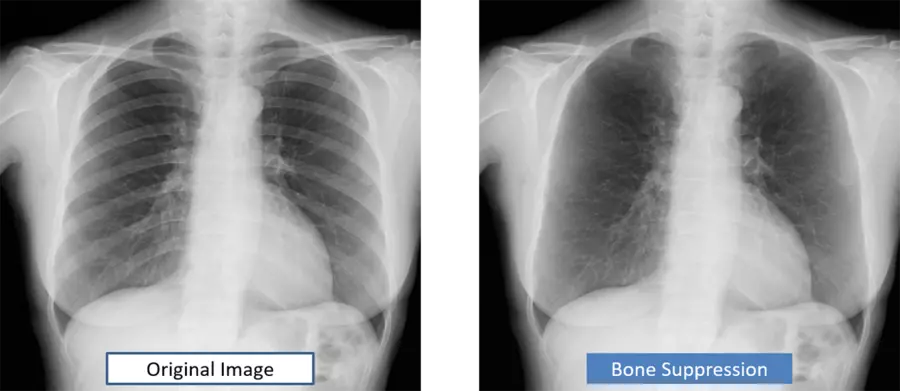

Функция подавления костей: Эта функция обеспечивает изображение, на котором, например, ключица и рёбра ослаблены. Это упрощает диагностику изображений грудной клетки